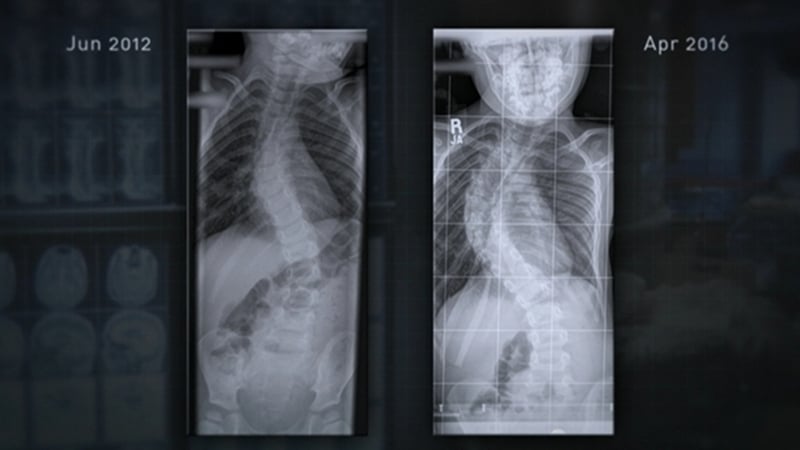

The mother of a 7-year-old boy with scoliosis has said that his life has been transformed since he had spinal surgery.

Darragh Cahill's battle for the corrective procedure was documented in RTÉ Investigates- Living on the List, which was broadcast earlier this week.